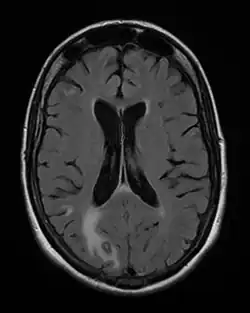

Os cistos contêm uma forma infectante do parasito, que é o bradizoíto, e em vez de se reproduzir rapidamente, formaram antes estruturas derivadas da célula que infectou, forte e resistente, cheia de liquido e onde o parasita se reproduz lentamente. Os cistos crescem e podem afetar negativamente as estruturas em que se situam, mais frequentemente músculos, o cérebro, no coração ou na retina, podendo levar a alterações neurológicas, problemas cardíacos ou cegueira, mas geralmente sem efeitos nefastos. Os cistos permanecem viáveis por muitos anos, mas não se disseminam devido à imunidade eficaz ganha pelo portador, inclusive contra mais oocitos que possam ser ingeridos. Se o indivíduo desenvolver ou for medicado para imunodeficiência, como após transplantes de órgãos, doenças auto-imunes ou na SIDA/AIDS, as formas ativas podem ser reativadas a partir dos cistos, dando origem a problemas sérios, com sintomas como exantemas (pele vermelha), pneumonia, meningoencefalite com danos no cérebro e miocardite, com mortalidade alta.